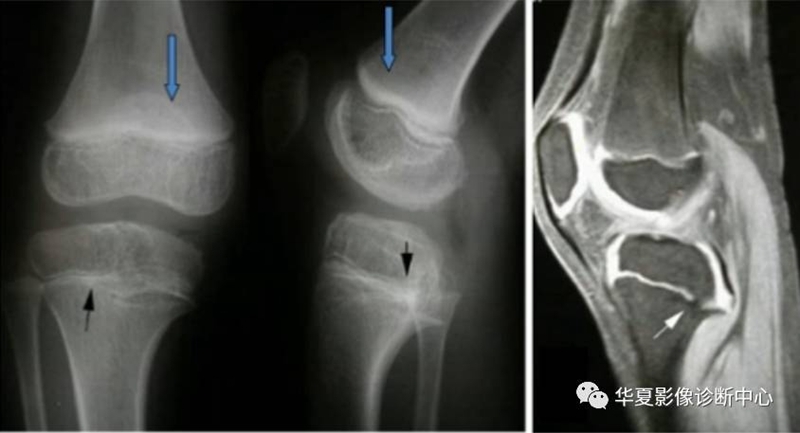

股骨远端正常骨骺,侵犯骺板软骨:出现软组织且宽窄不一